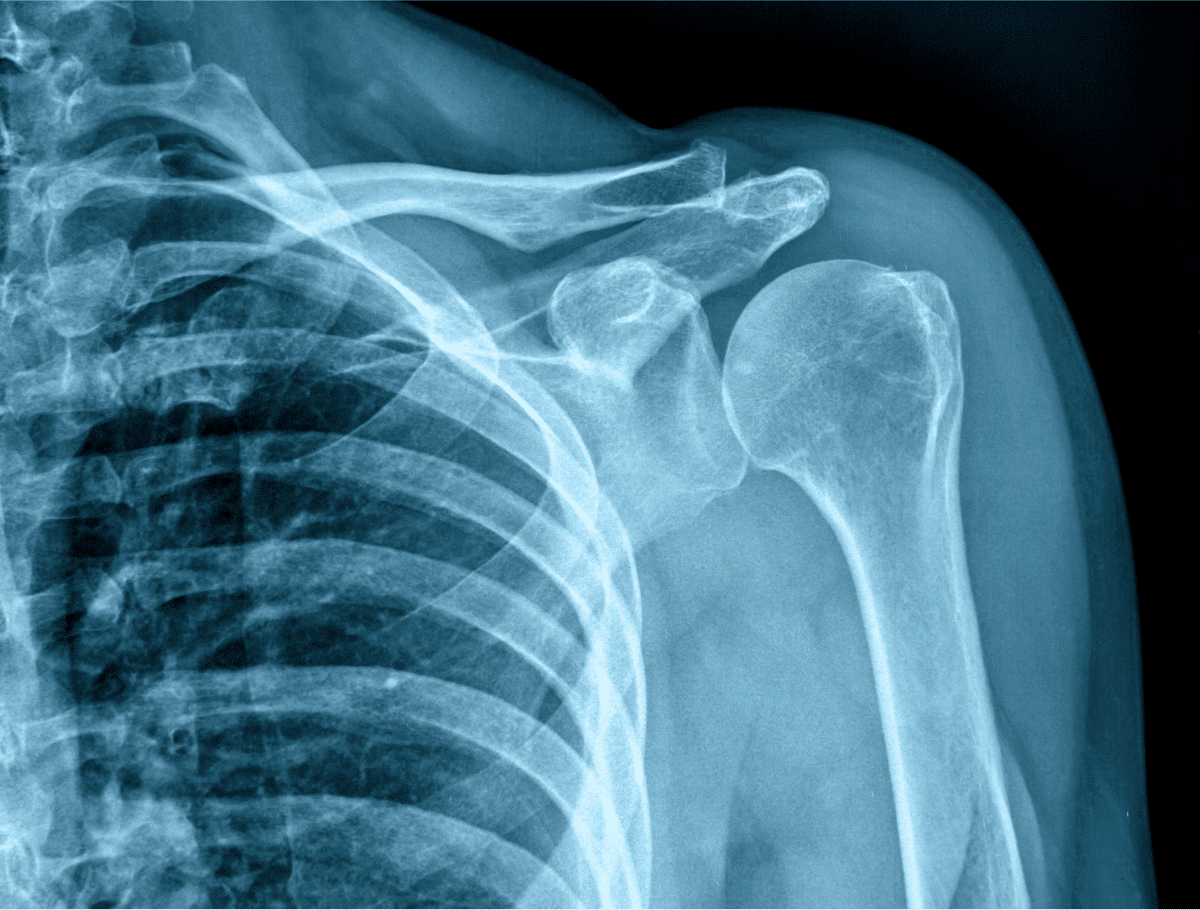

Given how quickly this virus has spread, it can be tempting to simply stop seeing your doctors and radiologist for the duration of the crisis. However, refraining from getting regular check-ups could put you at risk for other ailments that you would not be privy to otherwise. Radiology can detect cancer, trauma, cardiovascular/musculoskeletal diseases, metabolic diseases, neurosurgical diseases, and much more. Putting off your screenings can put you at risk, so it’s incredibly important that you continue your screenings.